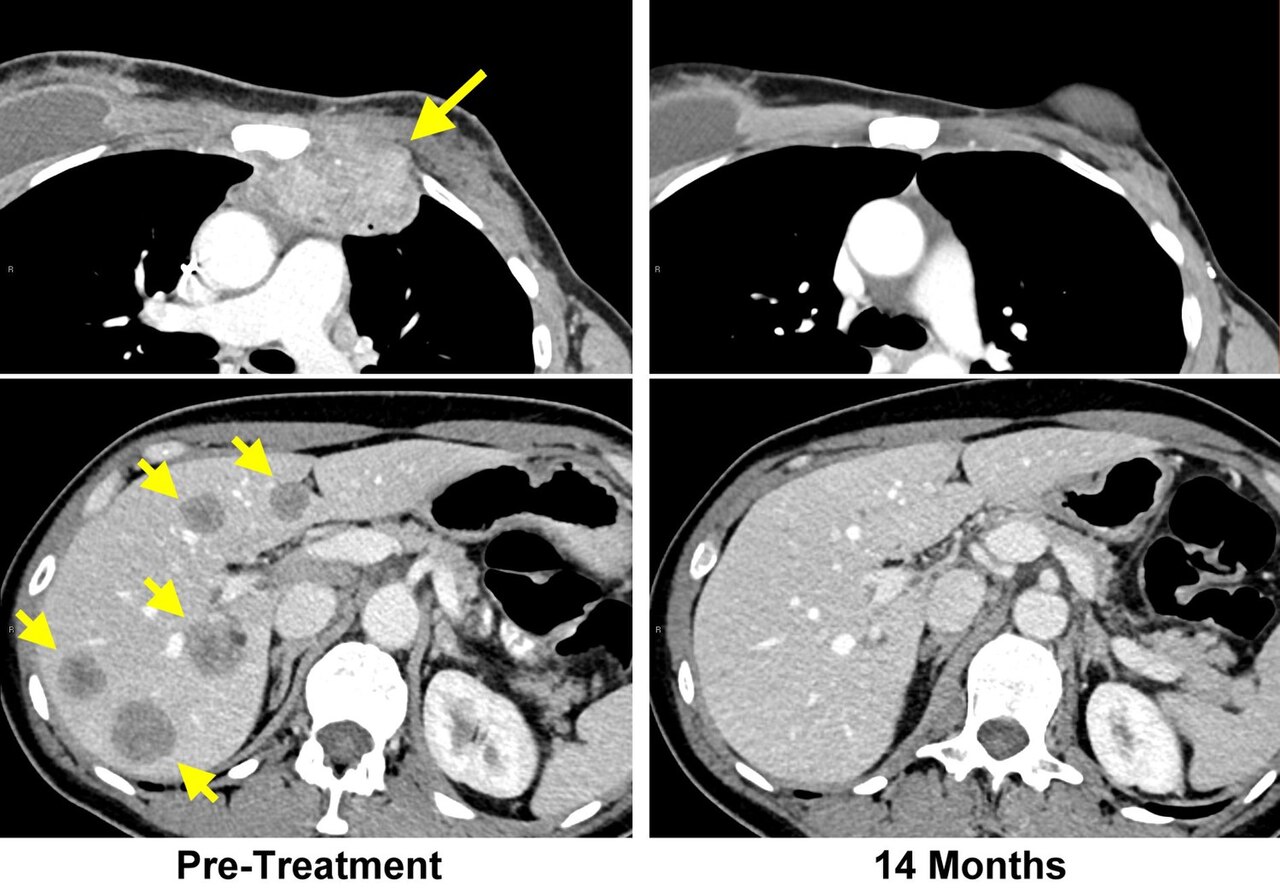

MRI — Chest/Cancer Staging

MRI scan used for cancer staging showing thoracic anatomy and lesion characterization

MRI Downloaded 2026-03-15

Mri

T1 Weighted

Wikimedia Commons: Cancer MRI Scans (28750336678).jpg